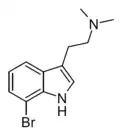

Substituted tryptamines, or serotonin analogues, are organic compounds which may be thought of as being derived from tryptamine itself. The molecular structures of all tryptamines contain an indole ring, joined to an amino (NH2) group via an ethyl (−CH2–CH2−) sidechain. In substituted tryptamines, the indole ring, sidechain, and/or amino group are modified by substituting another group for one of the hydrogen (H) atoms.

| Chemical structure | Short Name | Origin | Ring Substitution | RN1 | RN2 | Full Name | CAS Number |

|---|---|---|---|---|---|---|---|

| DMT | Animals, plants | H | CH3 | CH3 | N,N-dimethyltryptamine | 61-50-7 |

| 5-Bromo-DMT | Marine sponges, invertebrates | 5-Br | CH3 | CH3 | 5-bromo-N,N-dimethyltryptamine | 17274-65-6 |